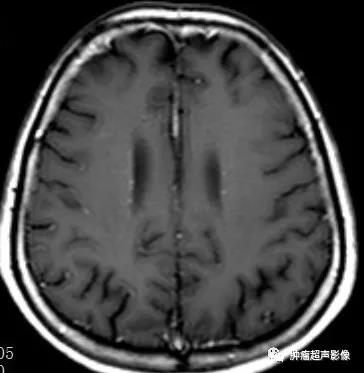

MR表现为两侧额枕叶皮层及皮层下多发结节或皮层增厚、脑回肥厚,FLAIR信号增高。

头颅CT示两侧侧脑室下多发小结节状钙化,增强MR示室管膜下结节明显强化。